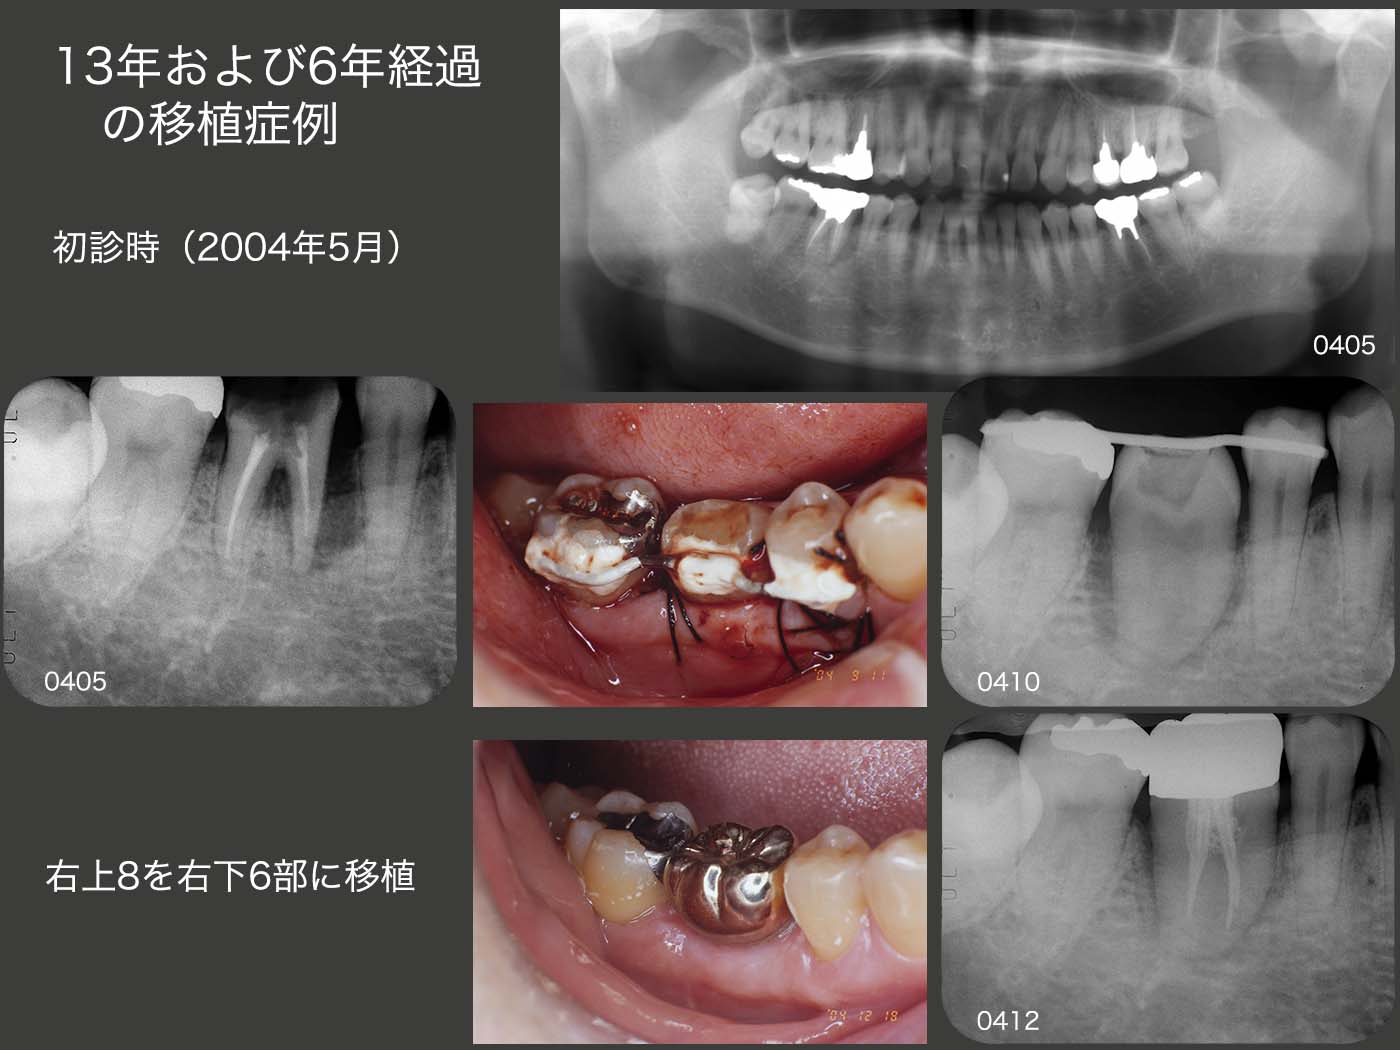

8.13年および6年経過の移植症例

2004年5月初診,54歳男性.主訴は右下6が腫れて痛い.近心根は歯根破折しており保存不可能であるが,遠心根は保存できる.しかしこの時は,右上8に歯根形態の良いドナー歯があることから,遠心根も抜去し,移植を選択した(04年9月).12月にクラウンを装着した.